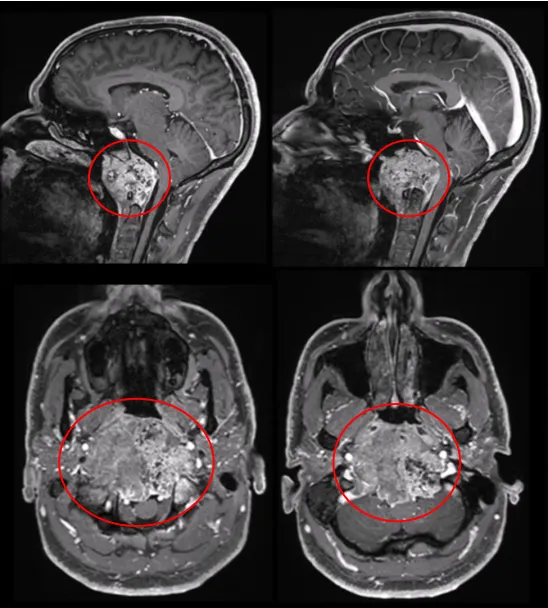

另一例福教授治疗的脊索瘤患者可能提供答案。肿瘤最大直径达10cm、体积96.5cm³,巨大肿瘤压迫脑干,福教授如何处理?术后是否进行放疗?

术前MRI显示肿瘤呈浸润性生长,向双侧后外侧扩展,右侧受累尤为严重。肿瘤侵袭至椎前间隙、下斜坡、双侧枕骨髁、第一颈椎C1前弓及C2齿状突。

为尽可能安全切除肿瘤,福教授制定综合治疗方案,术中除使用"筷子技术"外,还采用"双镜联合"技术。首先在显微镜下暴露肿瘤并进行瘤内减压,再使用神经内镜辅助探查,借助"筷子技术"切除对侧肿瘤。最后采用Roy-Camille技术进行枕颈融合术,为后续质子治疗创造无金属的定位和治疗通道。

综合治疗结果如何?患者无并发症发生,肿瘤得到完全切除。术后恢复过程中,患者吞咽功能显著改善,颈部疼痛同步缓解。8周后,患者接受质子治疗。

术后MRI显示肿瘤完全切除,脑干和延髓的占位性压迫解除。